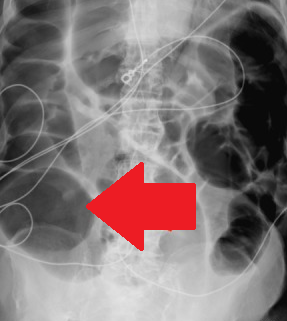

Απλές ακτινογραφίες κάτω άκρων, γονάτων και σφυρών. Ορατές ουσιώδεις ασβεστώσεις στην οπίσθια κνημιαία αρτηρία και ένα δίκτυο μικρών αγγείων στην οπισθοσφυρική περιοχή. Στα γόνατα, το αρθρικό διάστημα παρουσίαζε εμφανή ασβέστωση μικρών αγγείων. (Ευγενική παραχώρηση Dr. V. Penopoulos).